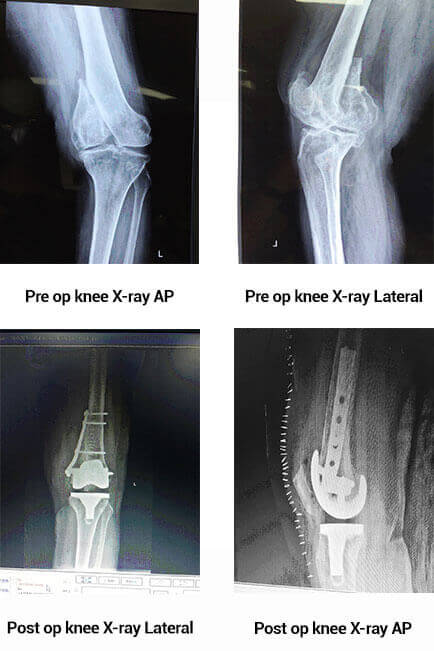

67 year old female patient came to Apollo Hospitals Chennai, complaining of knee pain and difficulty in walking. She had a history of trauma 16 years back which was treated with a cast and immobilization. She was evaluated with an X-ray and blood tests. Her standing knee X-ray showed mal united fracture distal femur with severe Osteoarthritis. She was taken up for Total Knee Replacement. Intra operatively it showed a non-union fracture distal femur. The fracture was then fixed and a Total knee Replacement was done. Patient was started on partial weight bearing walking from the next day and full weight bearing after 3 weeks.